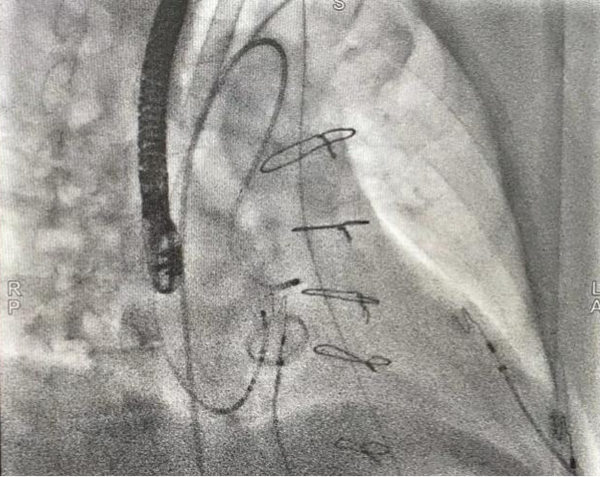

患者进入手术室麻醉后,室早消失,薛荣亮主任和李伟主任对麻醉药物精确滴定,既保证有稳定的室早出现,又保证患者的麻醉效果。超声室金鑫医师迅速实施食道超声插管。心内科郑强荪主任、王洪涛医师、郝广华医师和苏丹医师随即实施手术。首先穿刺股动脉,将消融导管逆行送入主动脉窦部位,在主动脉金属瓣上谨慎操作,行激动标测,未标记到室早最早激动点。考虑患者存在主动脉瓣金属瓣,消融导管不宜直接跨瓣膜操作,遂穿刺股静脉,在食道超声指导下行房间隔穿刺,将可调弯鞘管和消融导管依次送入左房、左室,以非同平面双弯角度最终把消融电极成功送入主动脉瓣下,标记到室早最早激动点。随着放电消融的“滴滴声”,10秒后,室早即刻终止。逐步增加功率,巩固消融后,室早未再出现,大家如释重负。术后持续心电监护显示,室早一个都没有出现,彻底解决了困扰患者多年的心悸问题。

主动脉瓣上激动标测

主动脉瓣下激动标测和射频消融